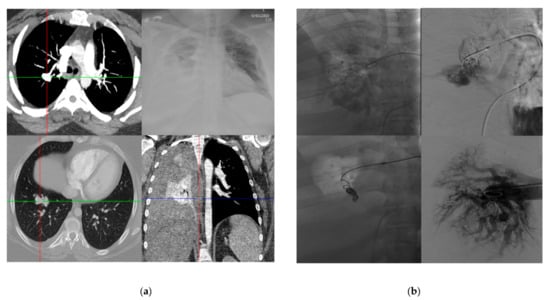

3.5. Treatment Outcomes

4. Discussion